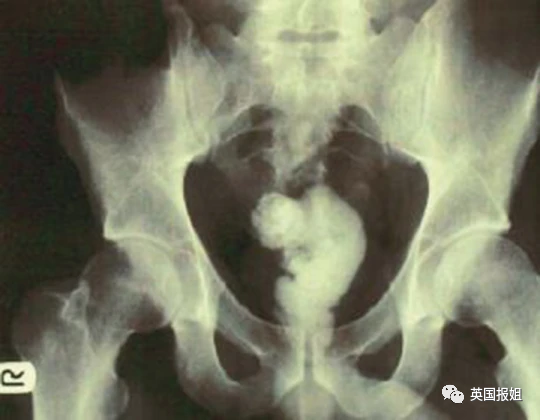

比如一把家门钥匙:

比如一个钳子:

比如手机:新闻报道称这名佐治亚州的忙碌男子,在把手机塞进身体后,仍不断接到电话,导致取出工作一度陷入僵局。

比如人人都知道放进去就取不出来的灯泡:

比如风评被害的巴斯光年:

当固体已经满足不了他们的时候,还有人毅然决然选择了流体:这名美国27岁男子用胶枪将融化的黏合剂给自己灌肠,黏合剂进入体内后迅速凝固,坚若磐石:

图中的患者是一名72岁的老翁,他自称在上厕所时不慎跌倒在了一个倒着的酒瓶上: